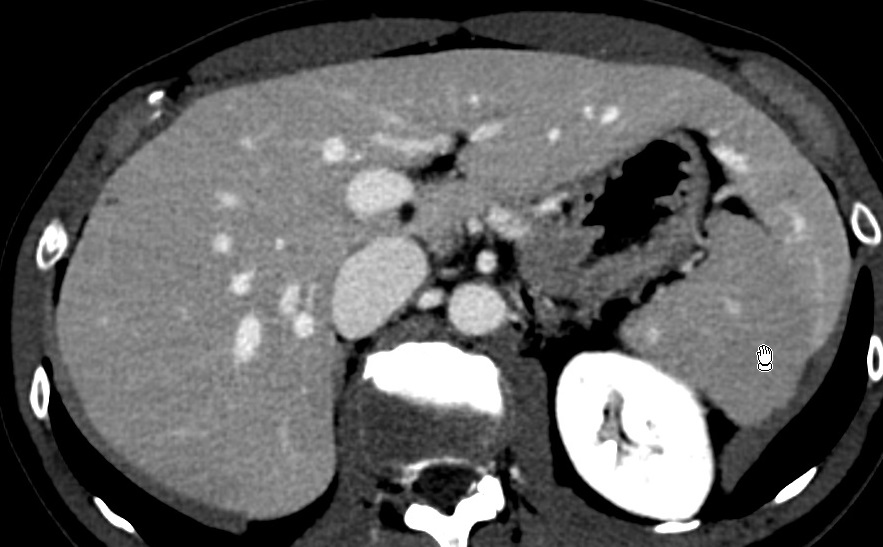

Beaver tail

hepatique bever beaver baver castor castorade hepatiques foie